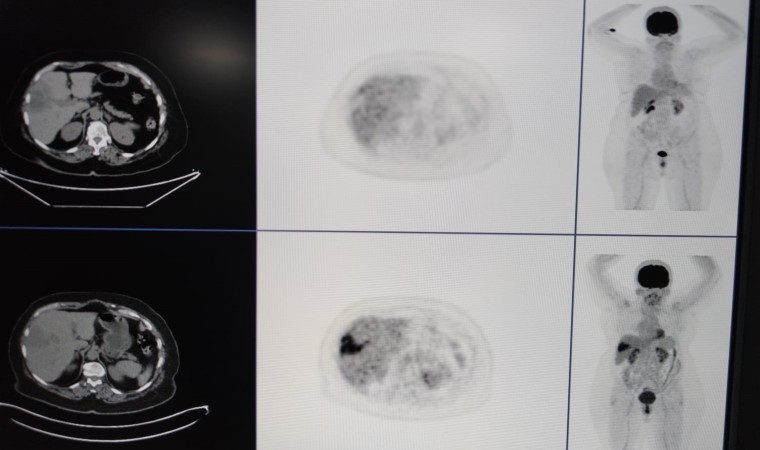

Diyarbakır Gazi Yaşargil Eğitim ve Araştırma Hastanesinde Radyoloji Uzmanı Ayhan Şenol, birimlerinde girişimsel radyoloji olarak hastalıkların tanısı, tedavisi ve takiplerini yaptıklarını söyledi. Hastaların biyopsi, sonografik ve tomografik yöntemlerle tanılarını koyduklarını dile getiren Şenol, “Genel olarak hastalığın bulunması için tüm işlemler yapılabilmekte. Hastalıkların biyopsi veya sonografik-tomografik yöntemlerle hastalıkların tanısını koyuyoruz. Bir kısmının da tedavisini yapıyoruz. TARE işlemi; belli organlardaki tümör hücrelerine hedef kitleyi besleyen damarın içine girip buna lokal olarak radyoembolizan dediğimiz maddenin enjekte edilmesiyle gerçekleşen bir işlemdir. Bu işleme yaygın olarak karaciğerin kendi tümörleri ile başka organlardaki tümörün yayılımlarını tedavi ediyoruz” dedi.

Nükleer tıp birimi ile işbirliği içerisinde hastalara tedavi uyguladıklarını ifade eden Şenol, “Bu servisimizde diğer birimlerle işbirliği yaparak çalışıyoruz. Nükleer tıp en fazla işbirliği yaptığımız birimdir. Hastaların çoğu buraya gelmeden nükleer tıp birimine görünüp öyle bize gelir. Hastanın uygunluğu araştırıldıktan sonra öncesinde burada tedavinin bir provası yapılır. Kitlenin besleyici damarı bulunup buraya bir prova olarak asıl vereceğimiz ilaca benzer bir ilaçla enjeksiyon yapılıyor. Daha sora nükleer tıp biriminde ilacın o kitleyi ne kadar tuttuğu hesaplanıp uygun dozlarda asıl ilaç dozu hesaplanır. Bir sonraki seansta aynı şekilde daha önce belirlediğimiz damarın içine girip radyoembolizan dediğimiz küçük parçacıklara radyoaktif maddeler yüklüyoruz. Biz bu parçacıkları küçük küçük doku içerisine gönderip hem belli bir süre tıkama hem de lokal olarak vücudun diğer taraflarına etki etmeden sadece kitleye etki edip onu öldürme yöntemini kullanarak tümörü tedavi ediyoruz” diye konuştu.